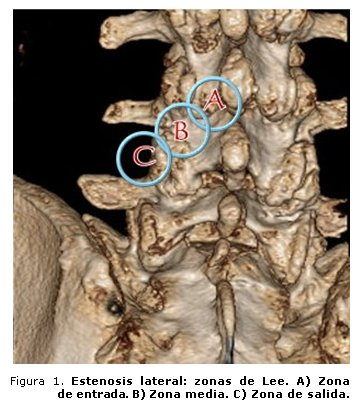

Canal lumbar estrecho

Muchos pacientes con canal lumbar estrecho permanecen sin síntomas hasta que otras patologías comprimen aún más el canal vertebral. Otros trastornos que pueden causar compresión incluyen los siguientes: